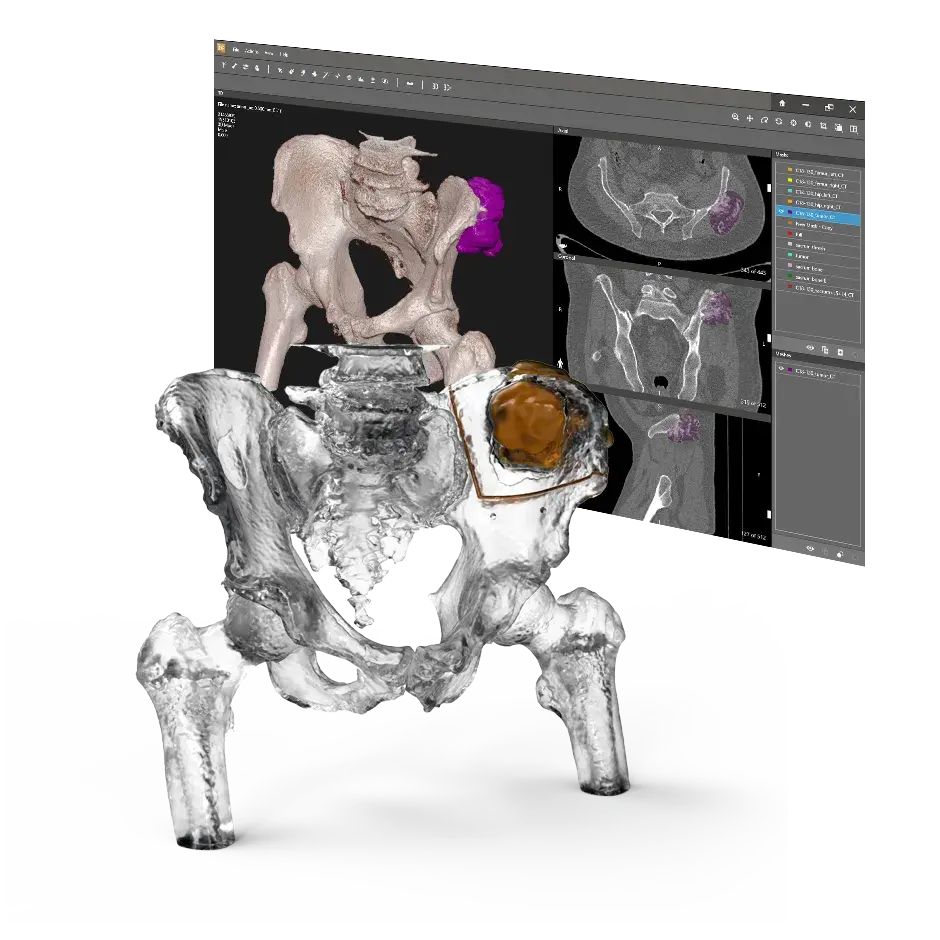

3D Systems partners with device manufacturers and healthcare providers to transform surgical outcomes for both patients and surgeons. We create custom solutions that help translate virtual surgery into the OR with the goal of improving outcomes and the overall patient experience. Our multifaceted offerings include advanced design and planning software, expert planning services and a full range of custom implants and instrumentation.